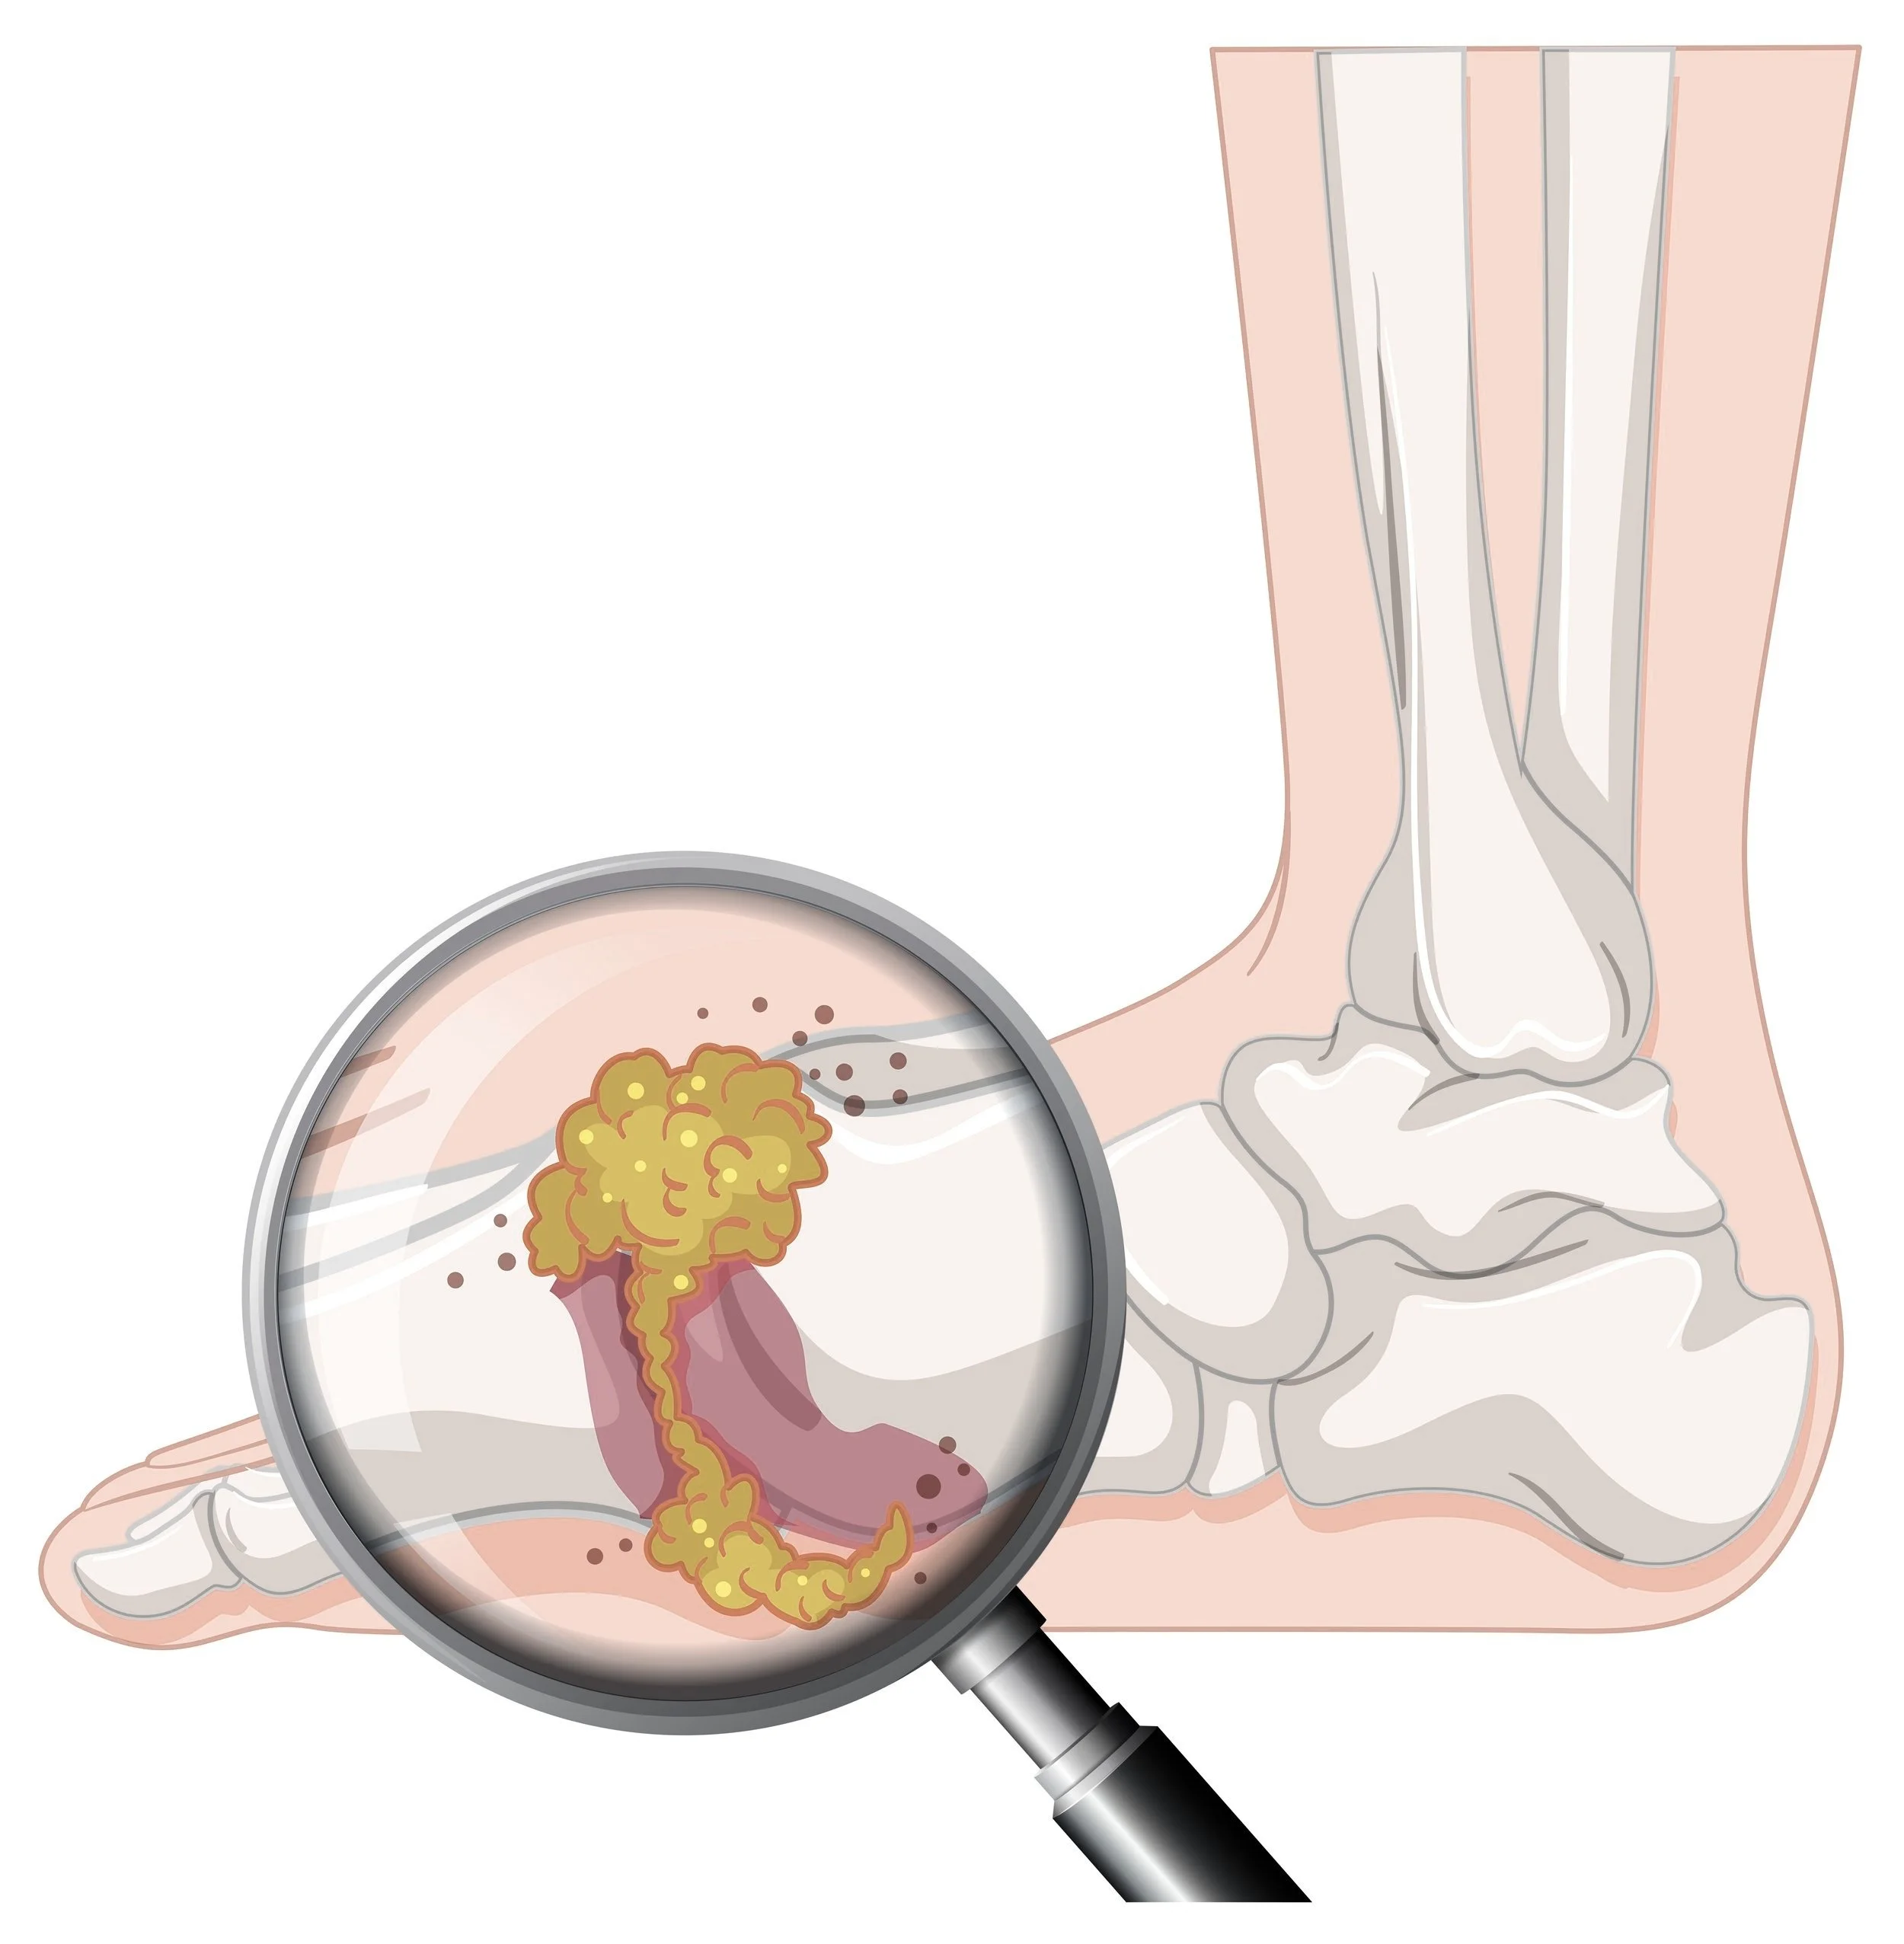

Gout is a type of inflammatory arthritis characterized by sudden and severe attacks of pain, swelling, and redness, usually occurring in the joints, most commonly the big toe.

It is caused by the accumulation of uric acid crystals in the joints, which can result from an overproduction or underexcretion of uric acid. Uric acid is a byproduct of the breakdown of purines, substances found in certain foods and naturally occurring in the body. The crystals trigger an immune response, leading to the intense pain and inflammation associated with gout attacks.